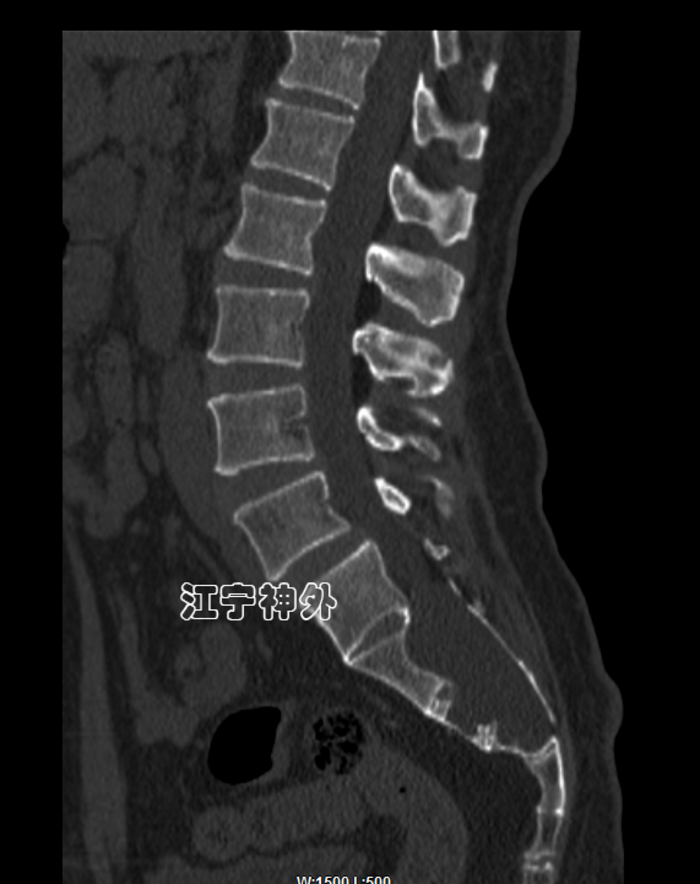

另外,由于巨大骶管囊肿的长期压迫,患者的骶骨已被广泛侵蚀破坏,无论是椎体还是椎板骨质都已大量损失,很多部位已经穿通。